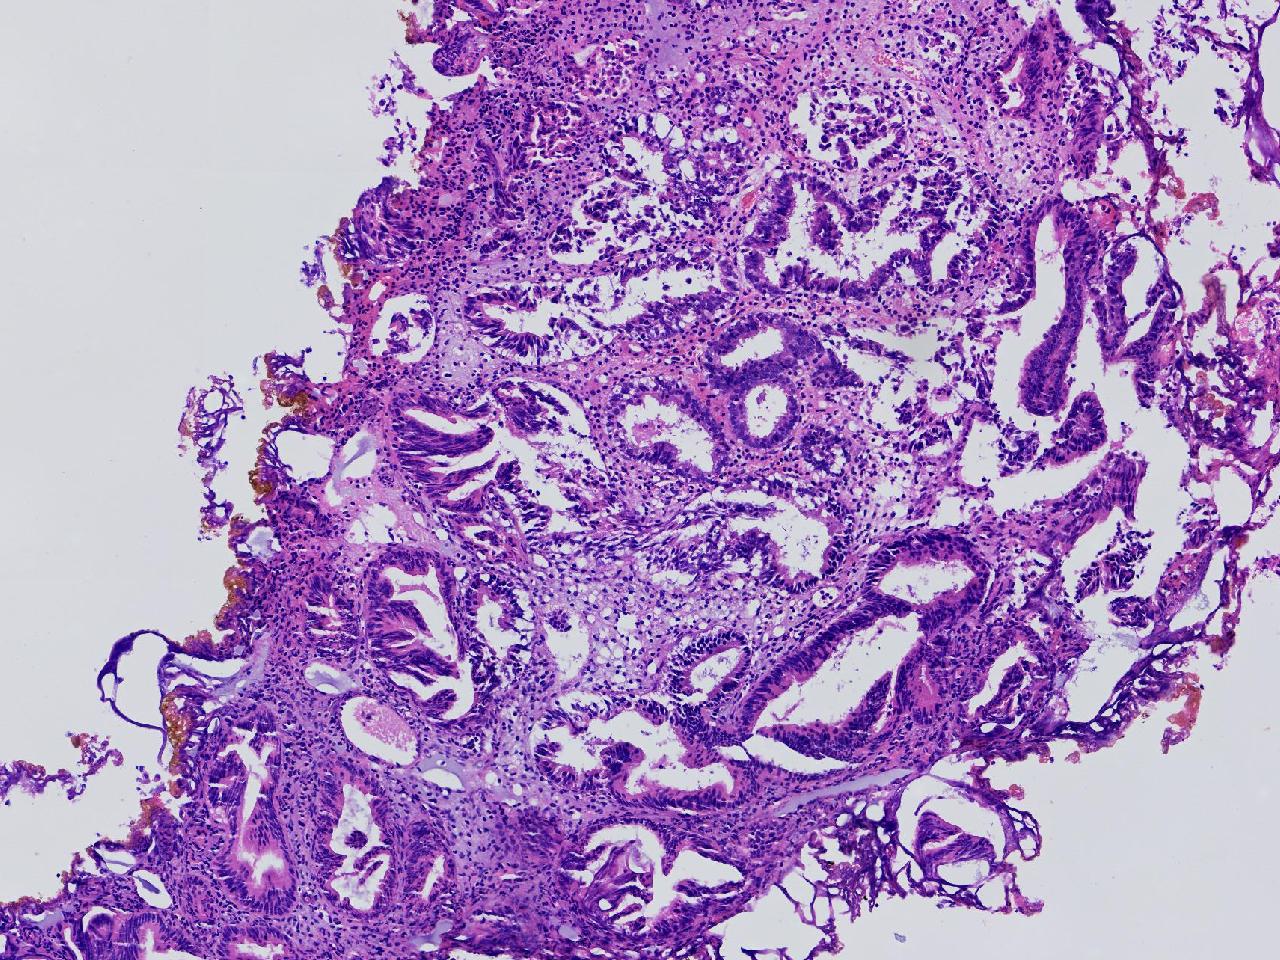

请教。1.有没有非典? 2.内膜是什么变化?

女,50岁,彩超示:粘膜厚度1.1cm。宫腔可见数个高回声,提示宫腔息肉。

子宫内膜+内膜息肉

灰粉色不整形软组织多块,3X3X2厘米。

子宫内膜息肉。

没有非典。

无非典型性子宫内膜增生,子宫内膜息肉

无非典内膜伴息肉。